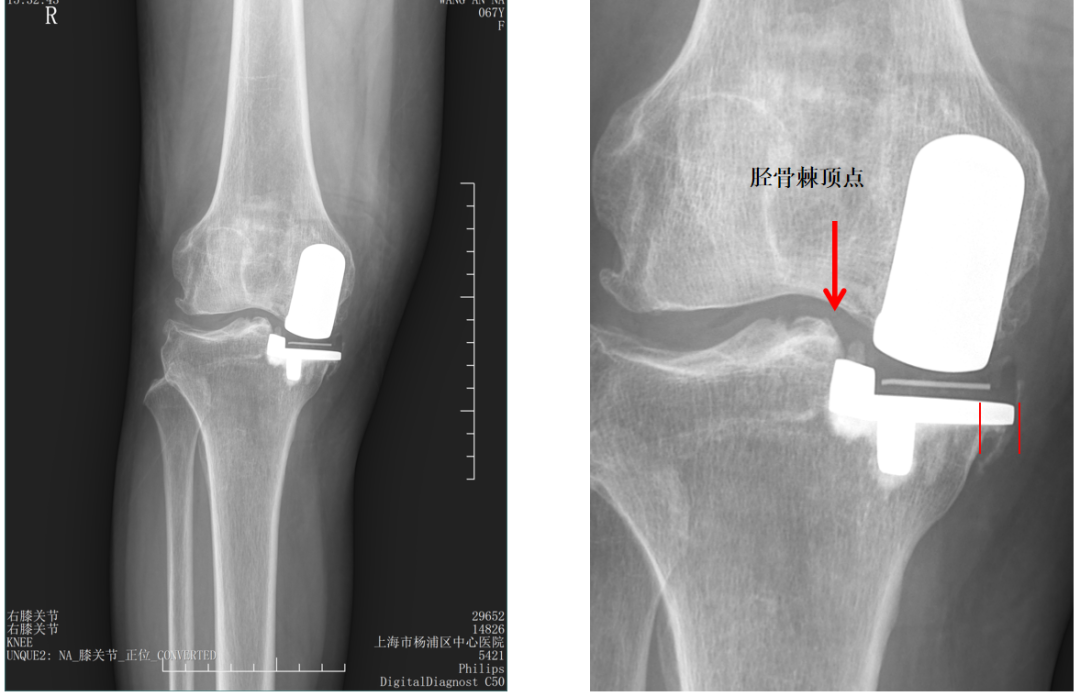

胫骨截骨宽度不足(距离顶点>2mm)

胫骨截骨跨越顶点